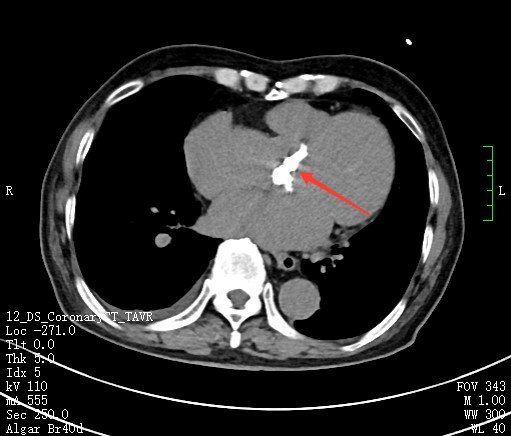

冠脉造影,红色箭头提示冠脉左回旋支严重狭窄